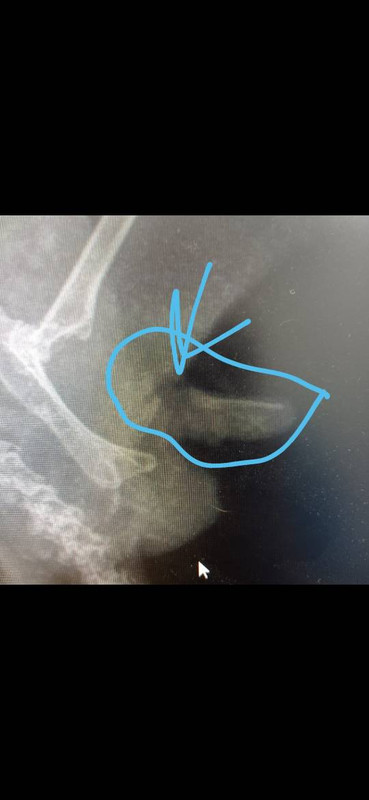

Добрый день. Мальчик 8 лет, живёт с пацаном 7 лет.

Образовалось волосяное кольцо, в запаре не заметили, когда увидели, там уже огромный отёк и всё налипло.

Поехали в ветеринарную клинику, сняли кольцо, вкололи байтрил,

когда сняли всё, там был виден уже некроз тканей.

Сначала мы 4 дня обрабатывали хлоргикседином и гидрокортизоном, потом уже отдали на стационар,

после 10 дней лечения на стационаре, отёк полностью спал, нормальный цвет вернулся, сегодня сделали рентген, врач сказал, что виден перелом полового члена. Сам членик не втягивается.

Рентген 16 сентября, фото 12 сентября. Сегодня не стал уже дёргать, и так рентген и тд.

Изображение

И ещё, может снимо не очень чёткий, но я переломов не вижу. Косточка полового члена лежит в толще органа и ни с чем в теле не соединятеся Она не входит в состав целого скелета, как ключичная полоска у кур, просто косточка. Отдельная от остального скелета. И она прямая, здесь не видно переломов.